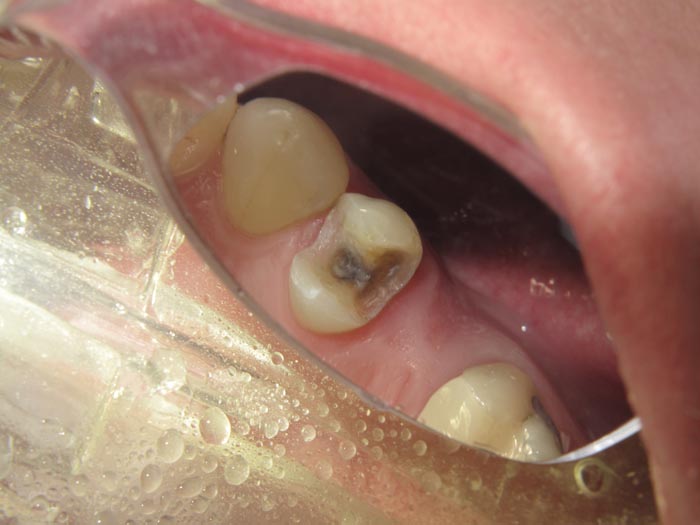

Case 3

A 62-year-old patient presented for restoration of #30.

• Figure 11

• Figure 12

• Figure 13

• Figure 14

• Figure 15